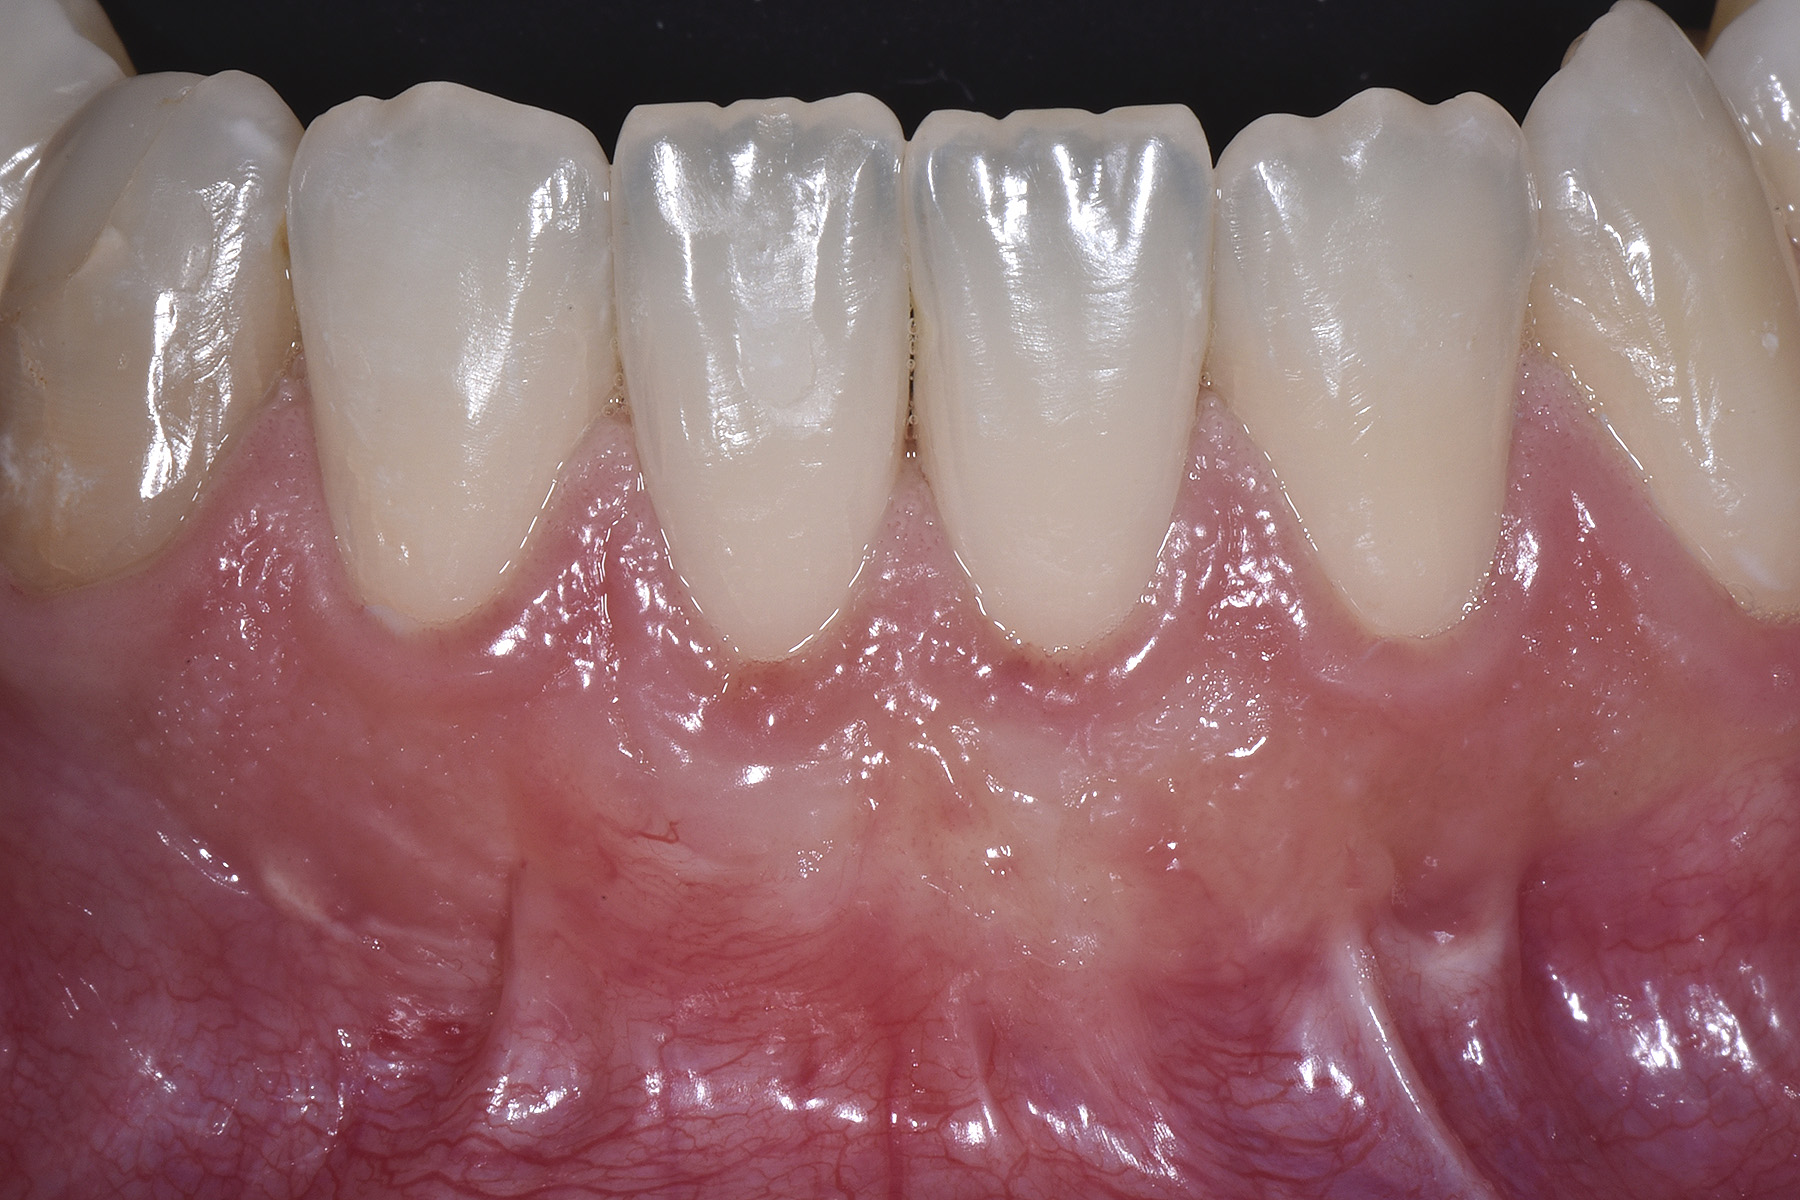

Vengono utilizzati 2 tipi di provvisori: il primo, cementato ai denti vicini, viene utilizzato dal momento dell’estrazione del dente fino ad impianto osteointegrato (circa 6 mesi); il secondo, avvitato direttamente all’impianto, ha una funzione di prova estetica ma soprattutto di guida per la maturazione dei tessuti gengivali peri-implantari portandoli verso la maturazione completa prima di posizionare la corona finale in disilicato di litio.